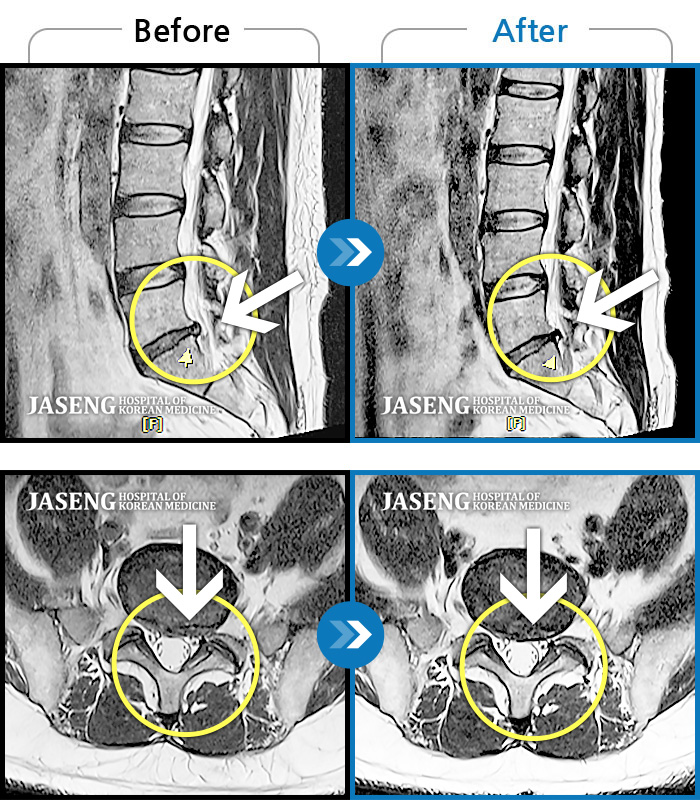

허리디스크

광주 · 장영우 원장

양측 허리부터 골반 묵직한 통증, 좌측 다리 외측까지 이어지는 당기는 통증으로 내원하셨습니다.

촬영시기

2503.04.01 ~ 2509.11.01

2025.09.22